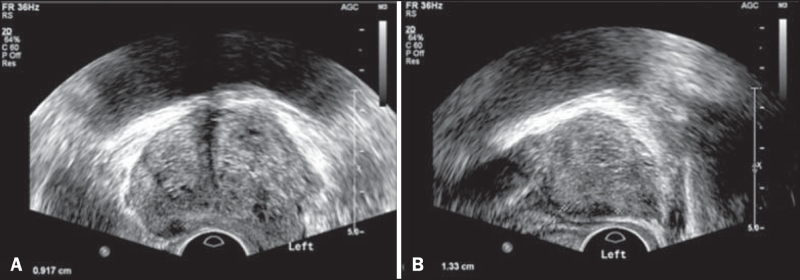

Trong giai đoạn sớm, hình ảnh siêu âm cho thấy các nhân tăng sản xuất hiện dưới dạng những cấu trúc giảm âm nhỏ, tập trung chủ yếu trong vùng chuyển tiếp của tuyến tiền liệt. Khi bệnh tiến triển, các nhân này có xu hướng phát triển cả về kích thước và số lượng, đặc biệt là theo hướng trước – sau, đẩy vào lòng bàng quang. Điều này khiến toàn bộ tuyến tiền liệt bị phì đại, làm mất đi hình dạng trăng lưỡi liềm trên mặt cắt ngang và thay vào đó là hình tròn.

Sự gia tăng kích thước của tuyến tiền liệt tạo áp lực chèn ép vùng tuyến ngoài (bao gồm vùng trung tâm và vùng ngoại vi). Tại ranh giới giữa phần tuyến bị chèn ép này, xuất hiện một đường viền có độ hồi âm rất giảm, được gọi là bao phẫu thuật. Đồng thời, các nhân tăng sản cũng trở nên không đồng nhất về mặt cấu trúc hồi âm.